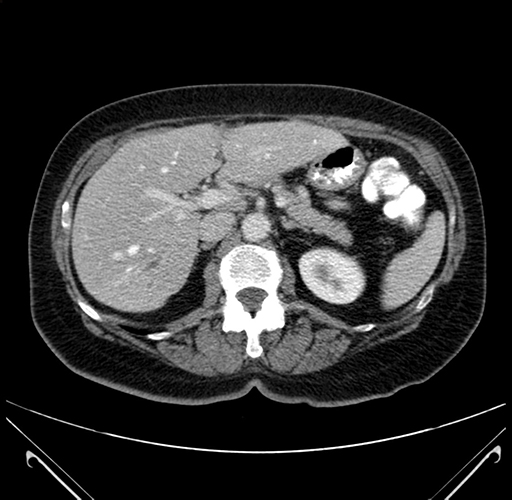

Pre-Chemo: Axial Venous

Axial Venous